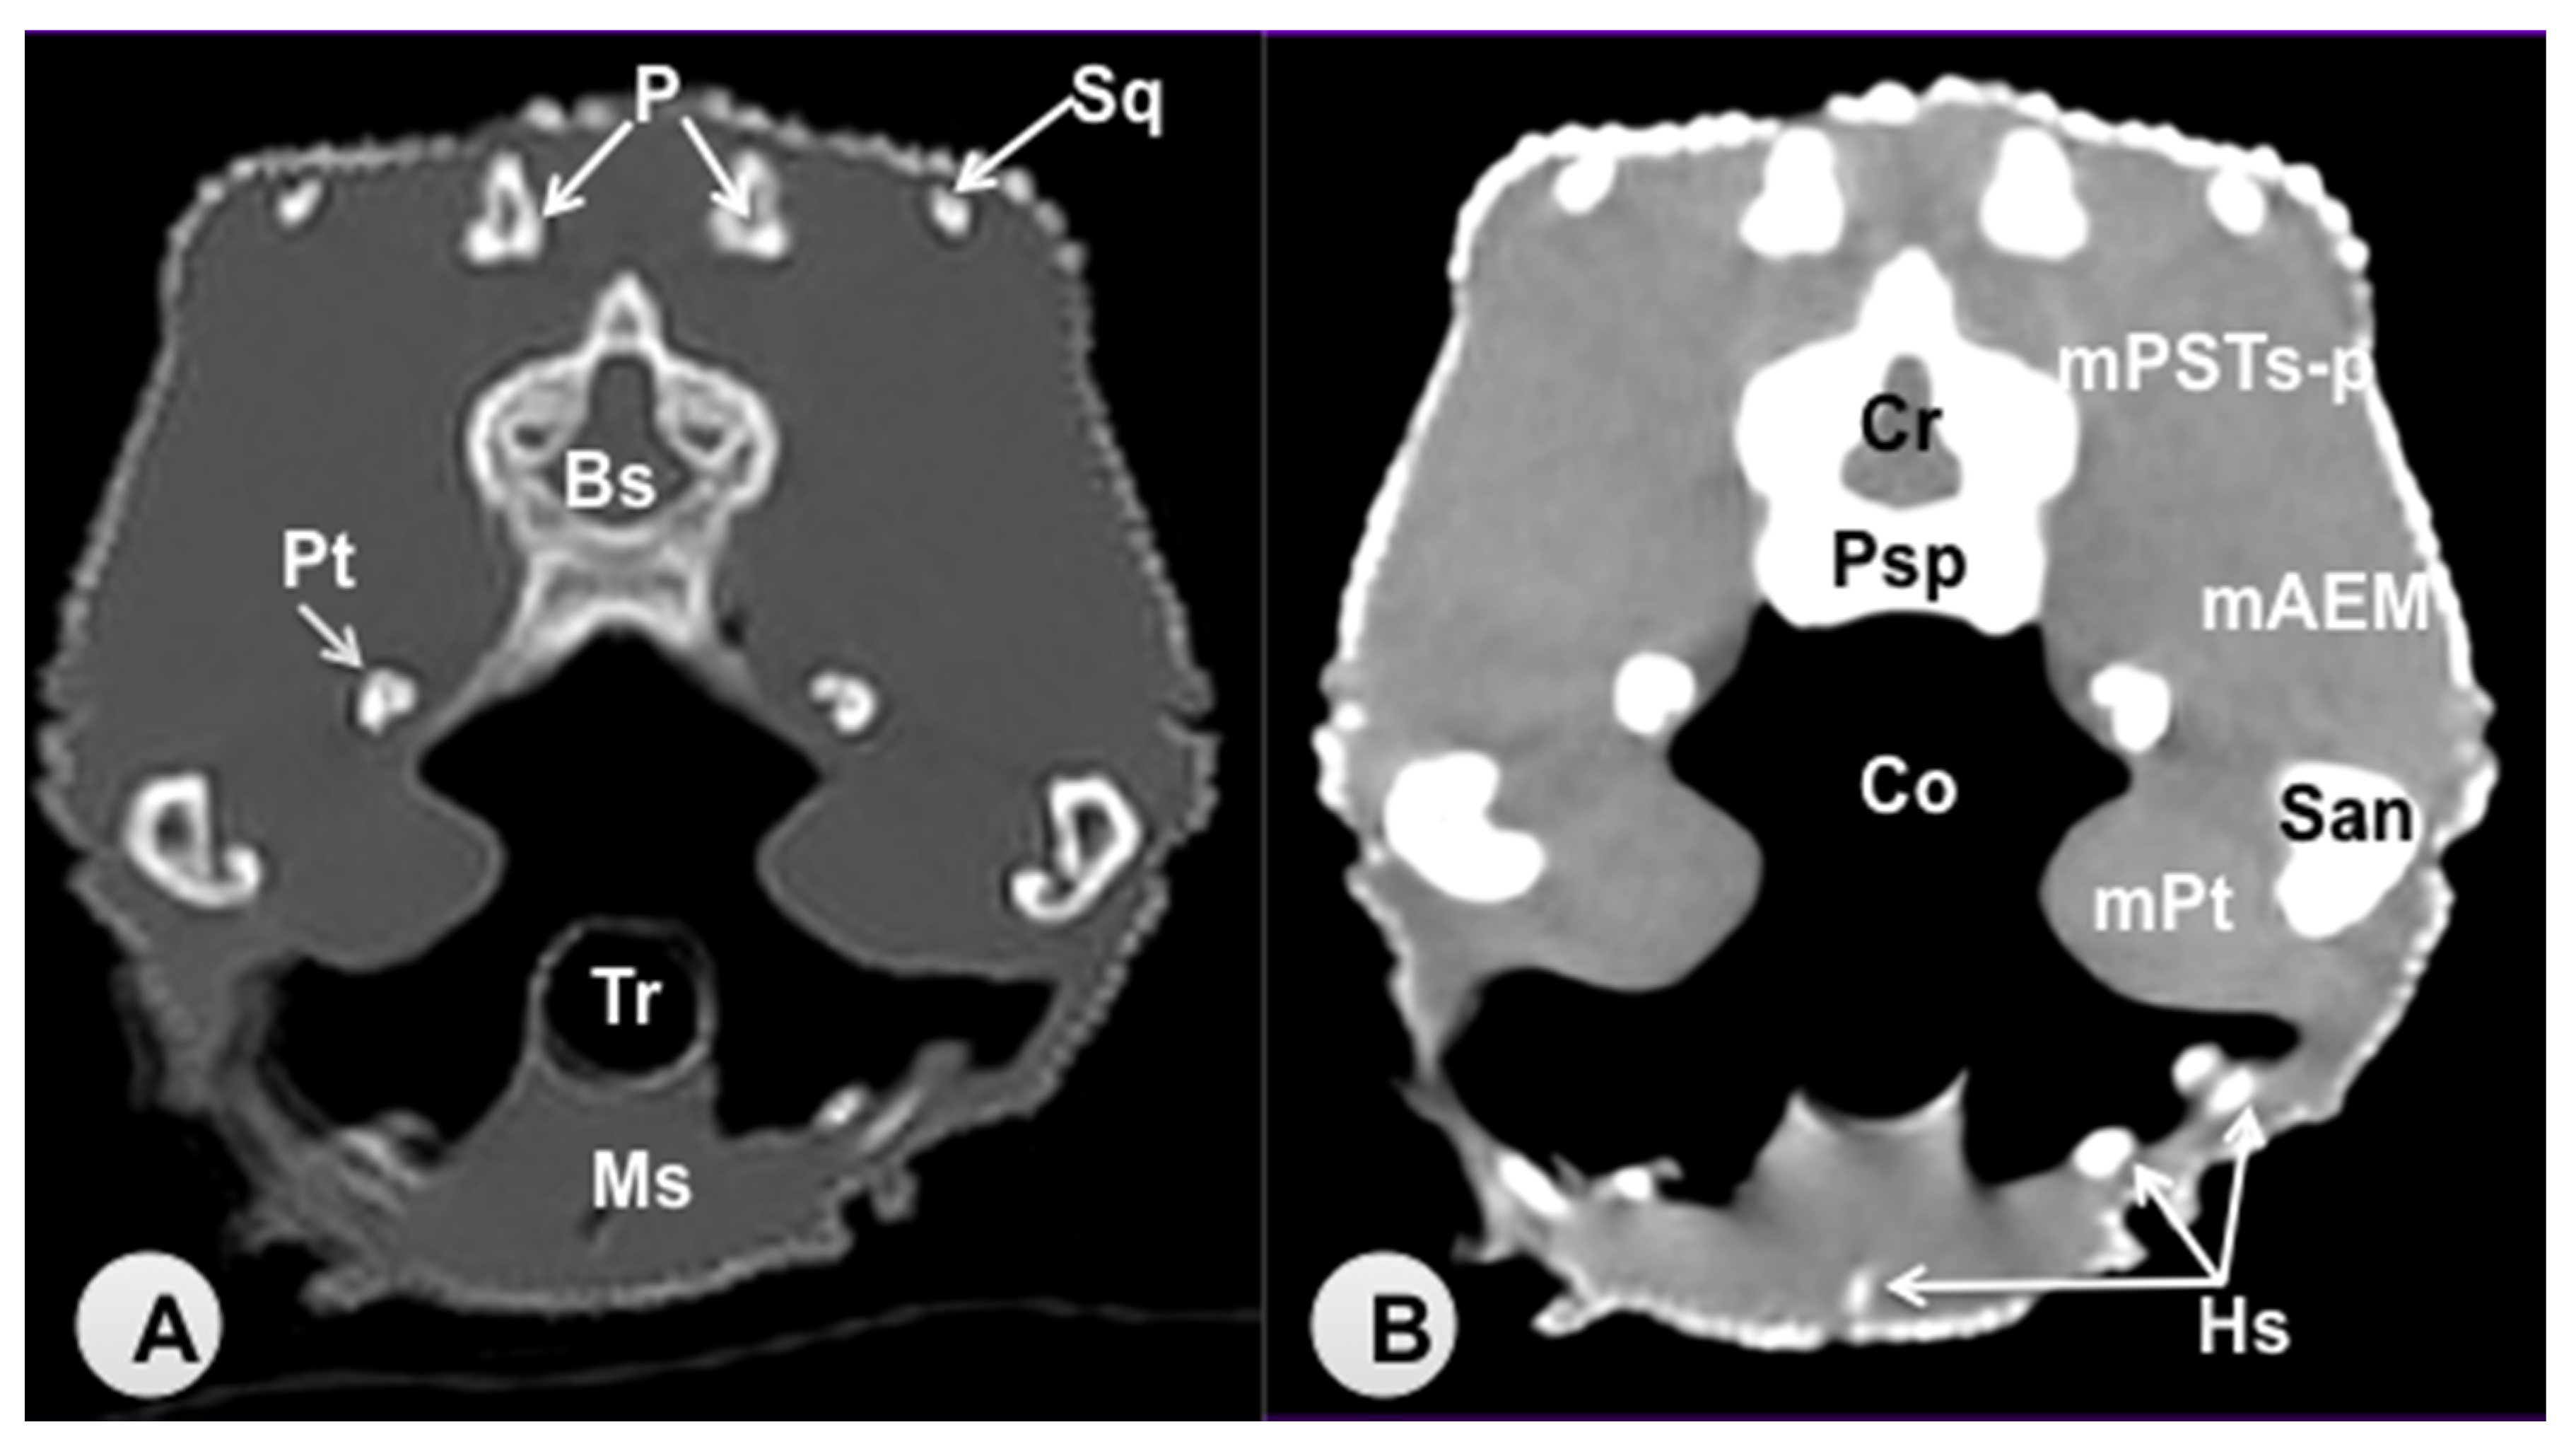

3.1. Transverse Computed Tomography Images